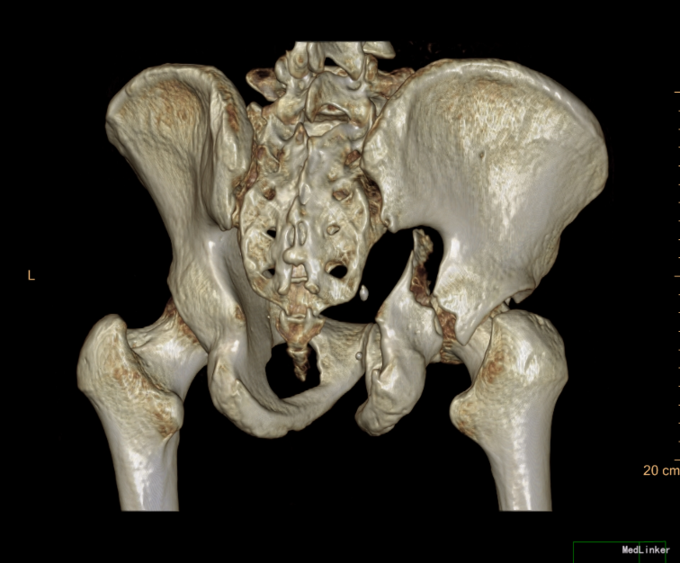

患者于2015年6月10日因车祸摔伤右侧髋关节,出现右髋部疼痛及活动受限。疼痛于活动后加重,休息可稍缓解。后就诊于营口市中心医院行骨盆三维CT示“右髋臼粉碎性骨折”,建议手术治疗,给予胫骨结节骨牵引术,患者于6月17日收入我院运动关节科病房,于6月19日转入我科。